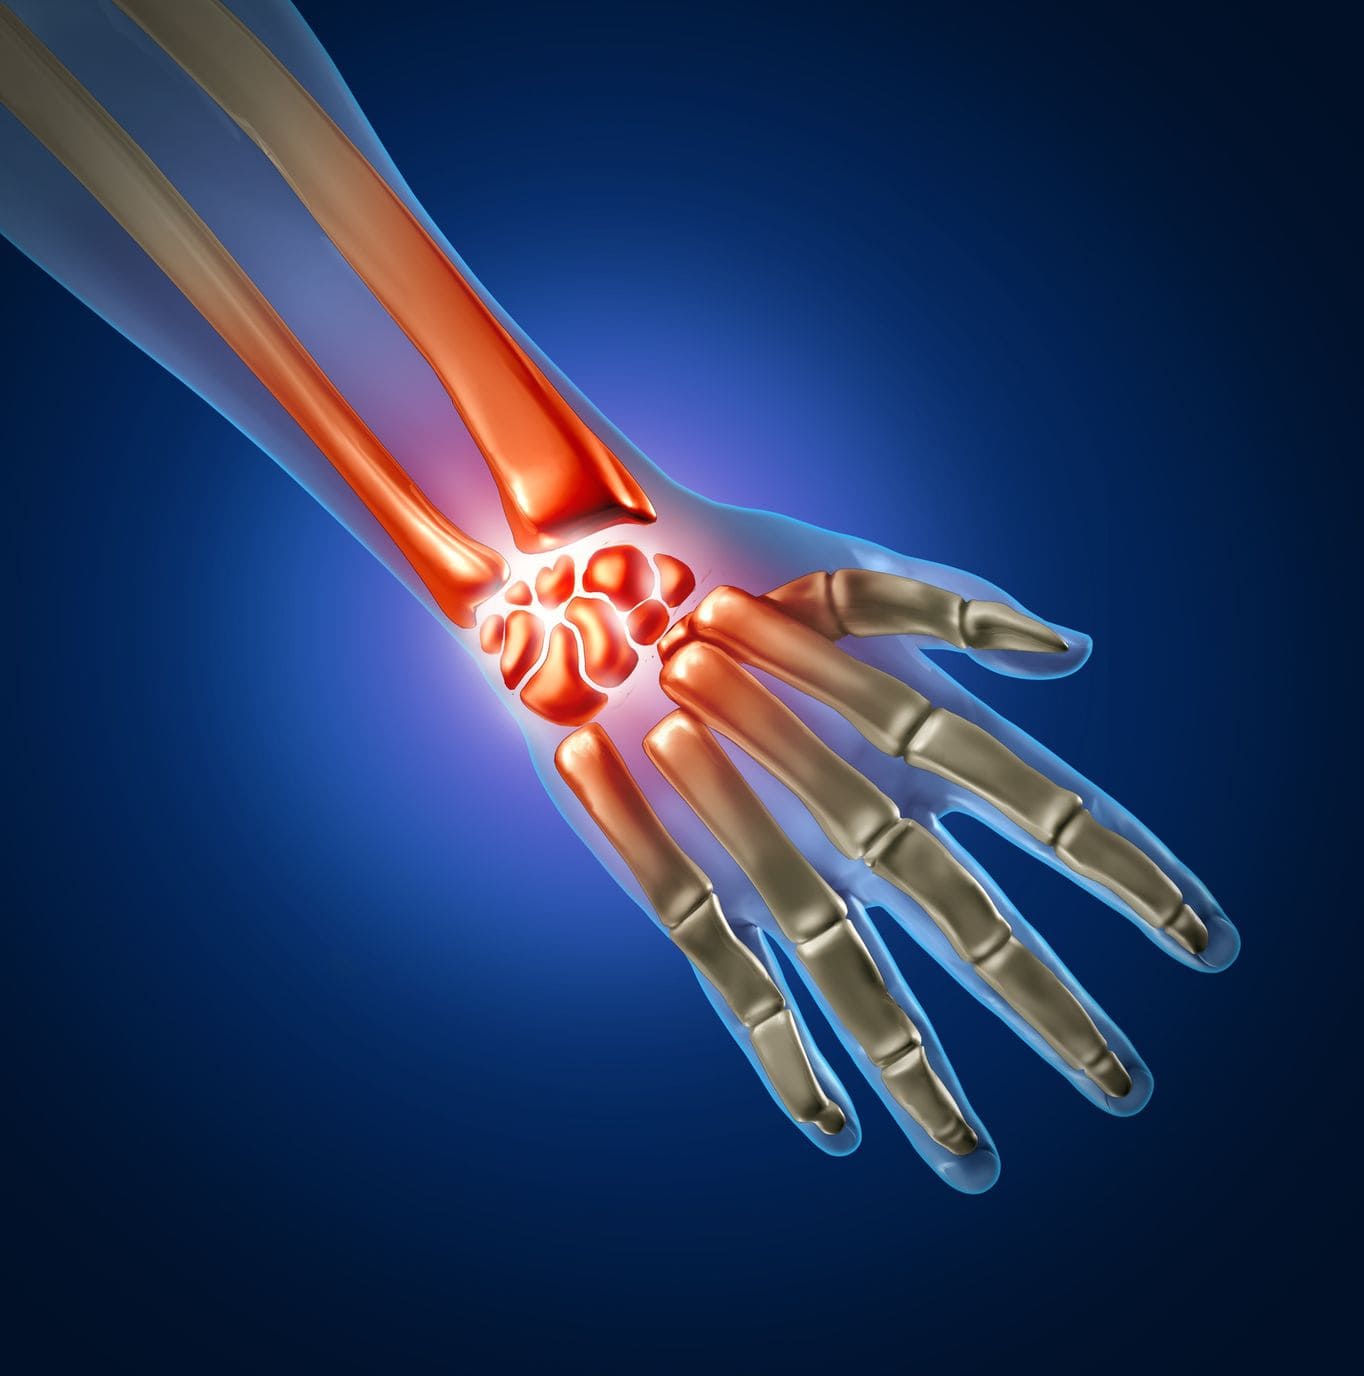

My special interest is in surgery of the shoulder, elbow and wrist.

I also perform all elbow and wrist surgeries including elbow replacement, Elbow fractures, wrist arthroscopy, carpal injuries like scaphoid fractures etc.